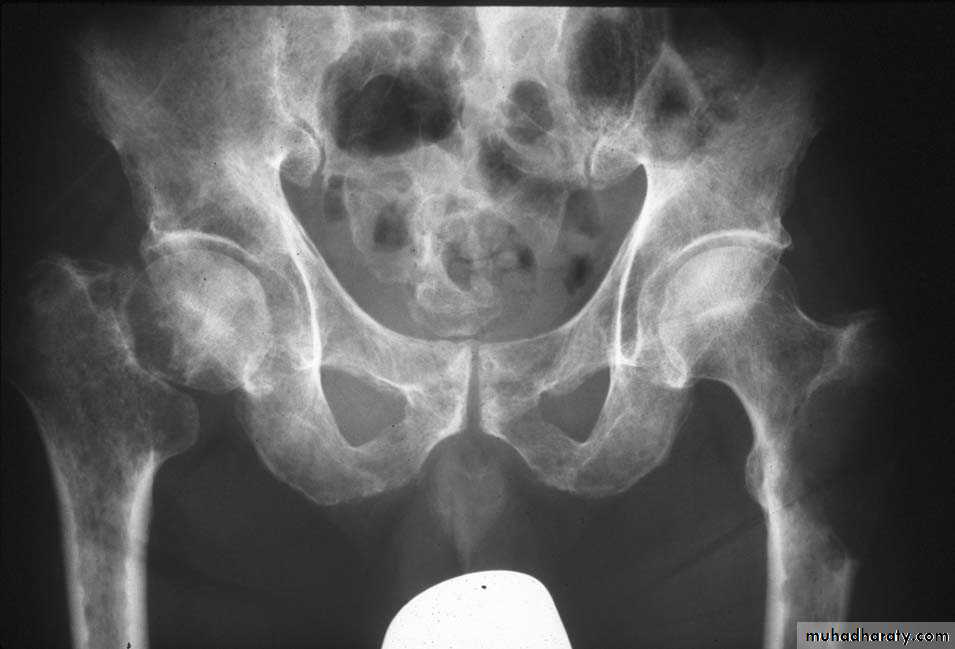

Hyperparathyroidism:

Excess parathyroid hormone secretion mobilizes calcium from the bones , resulting in a decrease in bone density , it may be primary from hyperplasia or tumour of the parathyroid glands or secondary to chronic renal failure. generalized loss of bone density.

. subperiosteal bone resorption.

. soft tissue calcification.

.brown tumour.